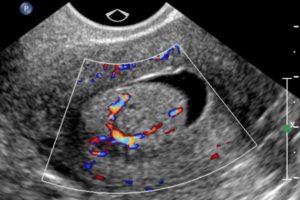

Дополнительными методами исследования выступают УЗИ, рентгенография, сцинтиграфия, МРТ и КТ и прочие.

Лучевая терапия может проходить дистанционно или быть внутриполостной (брахитерапия). Дистанционная лучевая терапия проводиться на линейных ускорителях (на фото).

При помощи брахитерапии возможно проведения больших доз облучения прицельно, в опухолевый очаг, не затрагивая здоровые ткани.

При проведении брахитерапии специальный аппликатор вводится в полость пациентке и посредством его, радиоактивный источник доставляется к цели.

Лучевая терапия в комплексе с химиотерапией становится единственно возможным методом лечения, так как рак носит местно-распространённый характер и не может быть удалён при помощи операции.Современные технологии позволяют использовать несколько видов лучевой терапии: внутриполостная и дистанционная.

Внутриполостная технология подразумевает контактное воздействие с опухолью, такими источниками как кобальт, цезий или иридий.

Дистанционное облучение необходимо в первую очередь для облучения регионарных лимфатических узлов и других возможных метастаз в области таза.